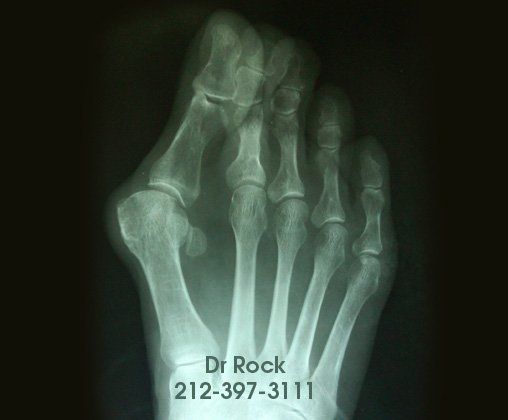

Get Beautiful, Pain-Free Feet

Take a look at our x-ray pictures of our recent footwork and see how your feet can benefit.

Whether you want to improve the look of your feet or need to relieve pain,

you can find out the best option for you with our FREE phone consultation.